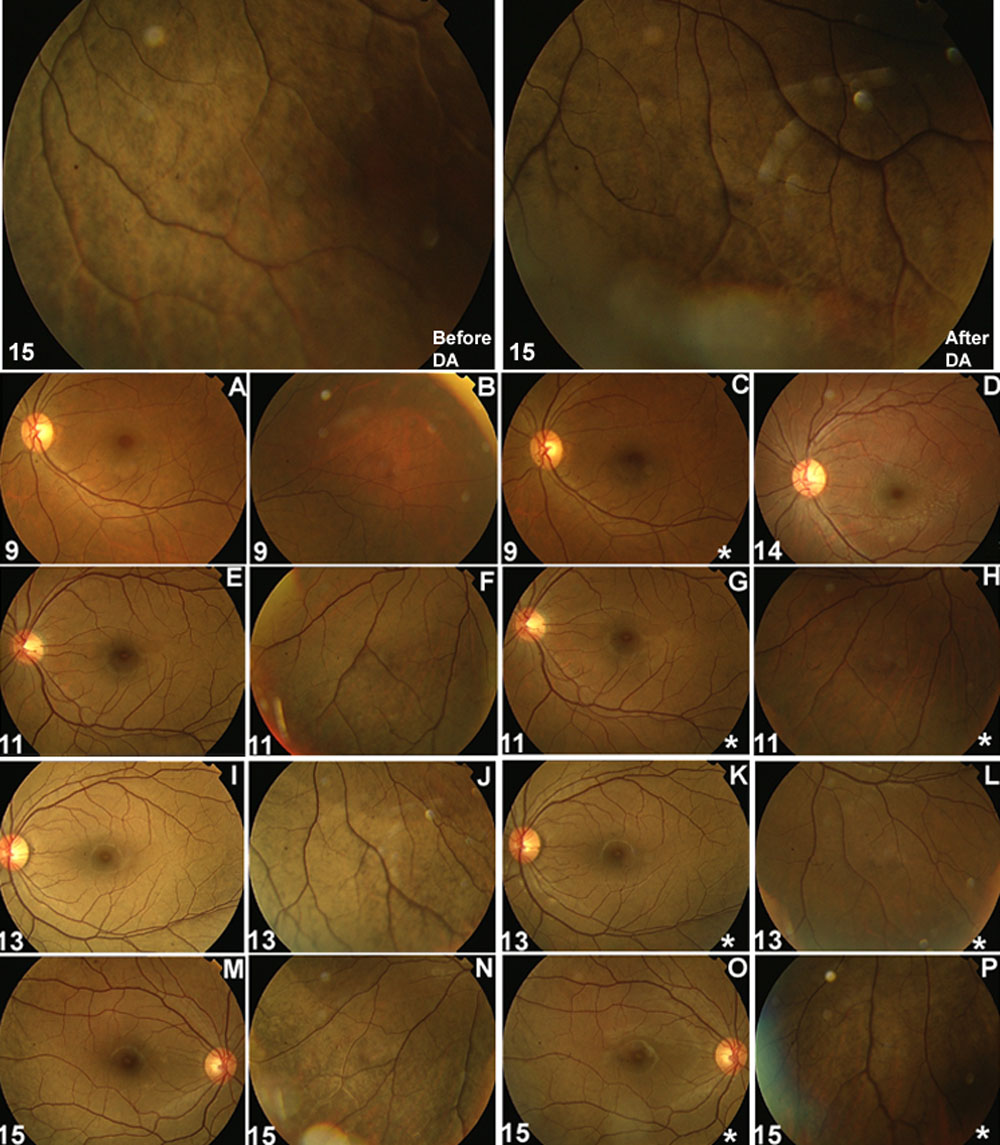

Figure 2. Fundus photographs before and after dark adaptation

Fundus photographs from two carriers (numbers 9 and 14) and three patients (numbers 11, 13, and 15) taken under ordinary light and after 4 h of dark adaptation (DA). The number on lower left corner represents the individual identification number as shown in pedigree on Figure 4. Photos with an asterisk (*) on the lower right corner were taken immediately after 4 h of dark adaptation. Generalized carpet-like retinal degeneration on the peripheral retina before (top left) and after (top right) 4 h of dark adaptation. Such peripheral retinal changes presented in all three affected individuals. A silver-gray or golden-yellow metallic sheen of the fundus or retinal vessels standing out in relief against a radiant background was not obvious in any of the patients. There were no obvious changes of color after 4 h of dark adaptation in affected individuals number 11 or 15.